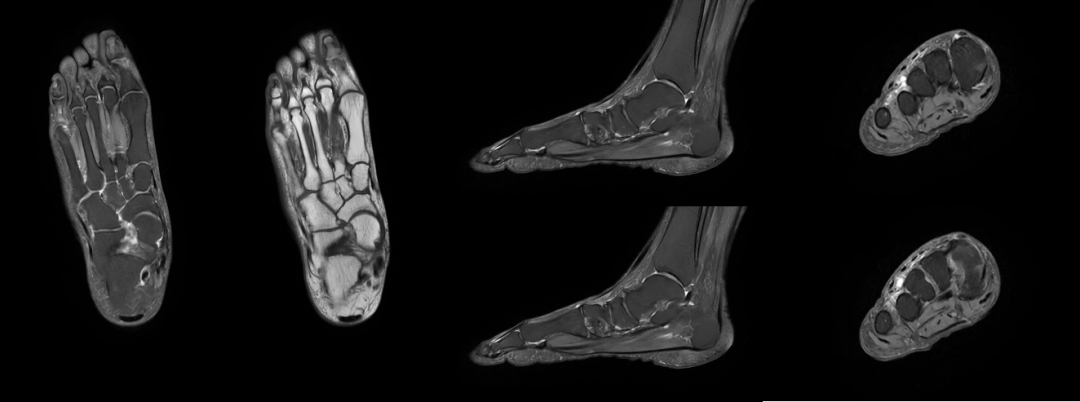

骨关节:膝关节半月板/韧带损伤、肩袖撕裂、股骨头坏死等;

膝关节

肩关节